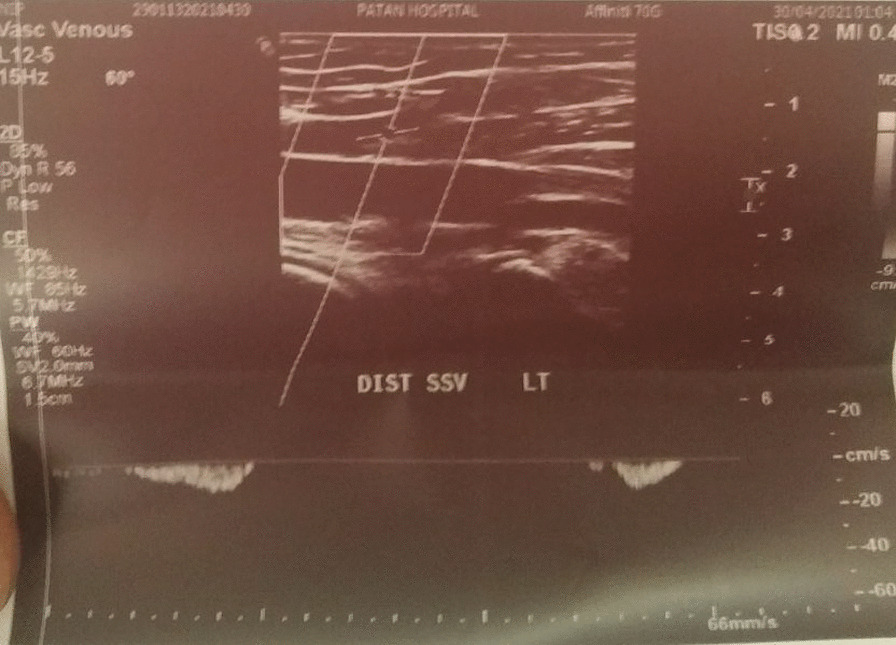

Fig. 2.

Doppler of distal end of Superficial Saphenous Vein

Details: Echogenic thrombus causing complete narrowing of proximal 1/3rd of SSV was noted, with almost similar findings in previous Doppler report. The thickening of the proximal part of SSV was 3.5 mm in diameter (Fig. 1) whereas that of the distal part of SSV was 2.4 mm in diameter (Fig. 2).

Venous Doppler USG left leg:

Report of Date: May 03, 2021.

Superficial Chronic thrombotic Changes of SSV.

Details: Acute thrombus partially occluding lumen of proximal SSV. SSV distal thrombus could not be assessed.